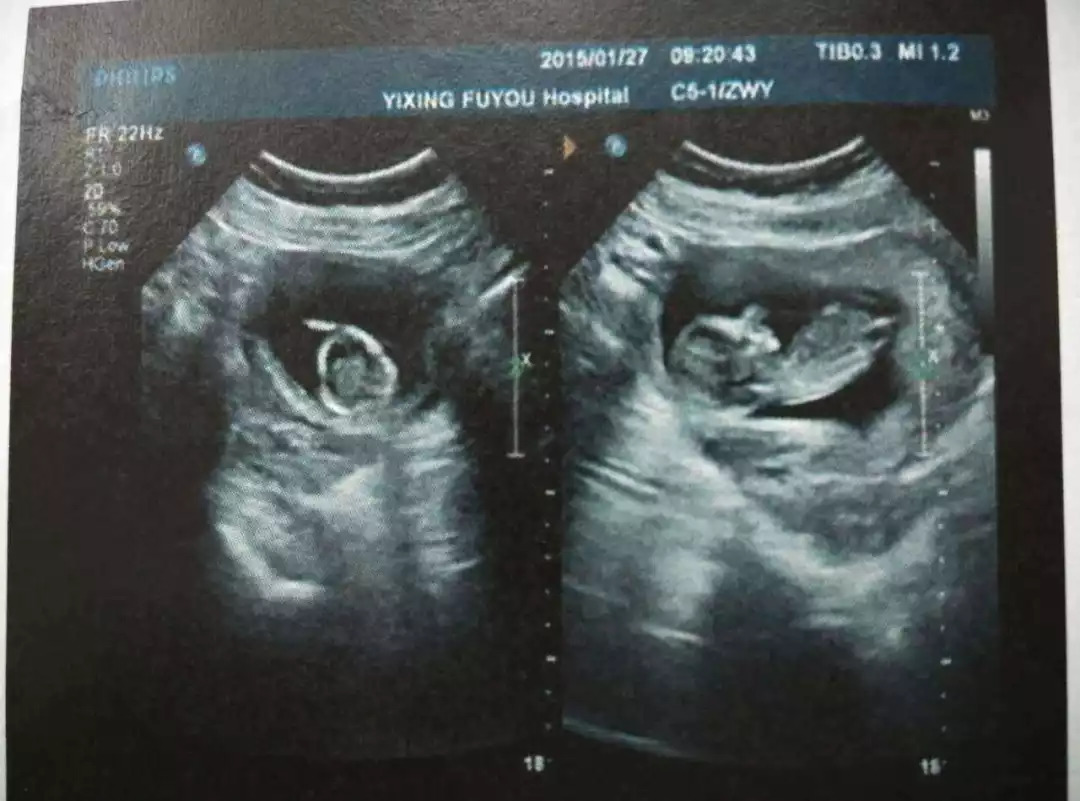

正当所有人都满心高兴时,毫无预兆地,4月11日黄莉文在上班途中感觉明显不对劲,次日赶到产检医院一看,果然出问题了:B超检查发现她的宫颈管变小兼且呈现扩张。是宫颈机能不全!她随即被收治住院进行保胎,此时,腹中的宝宝只有21周。

果然,4月24日,黄莉文发现自己有少许阴道流液,于是赶紧告诉医生。医生检查后发现,羊膜囊已经突出于宫颈外口,大小约3*3cm,此时B超也显示宫颈管分离!